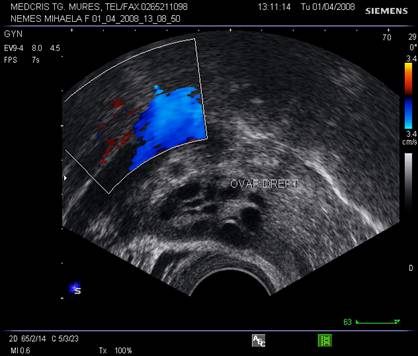

Ovarele. Sectiunea longitudinala directa, spre peretele lateral pelvin, la ecografia transvaginala, pune in evidenta ovarele cu forma elipsoidala. Acestea au structura ecografica relativ slab ecogena, in apropierea si sub vasele iliace.[5]

examen Doppler tumoral sau al organelor genitale interne,